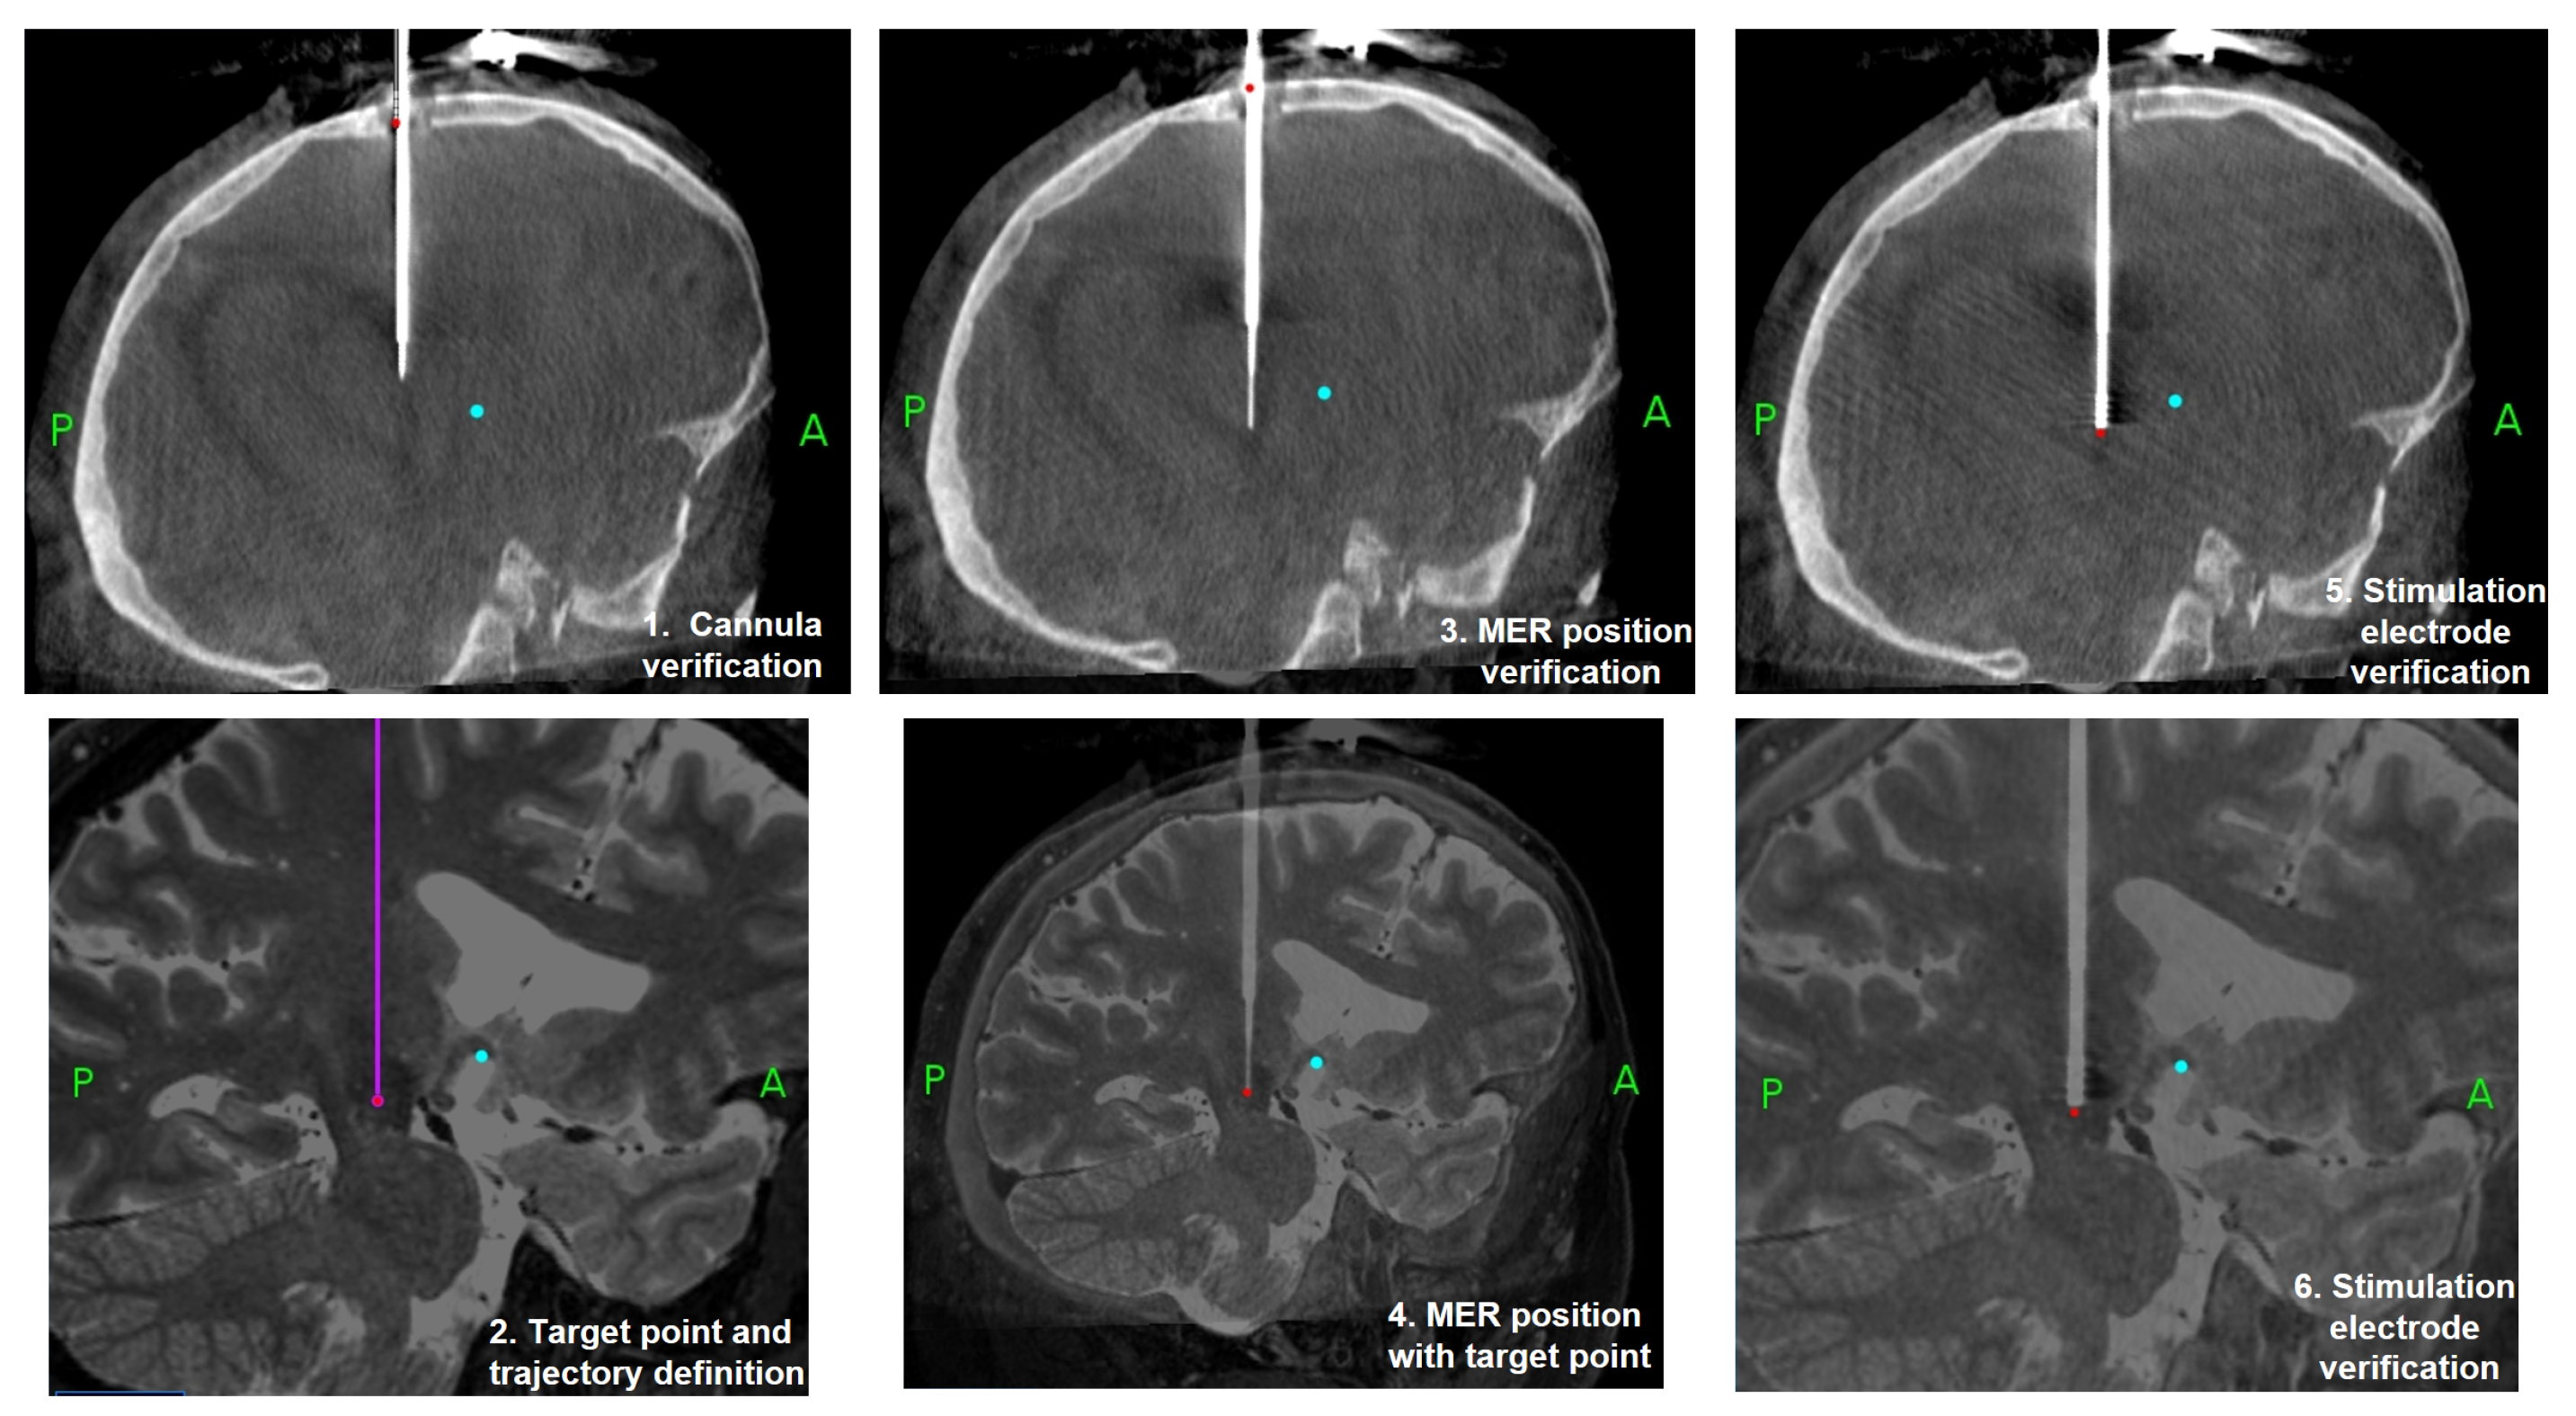

Figure 1 shows the DBS surgery process in six steps. With the patient under general anesthesia, an orifice is made in the skull, a cannula is inserted, and it is verified that the inserted position is adequate to reach the estimated position of the STN. Second, the initial target position is traced. Third, MERs are inserted and a verification that MERs are inserted is made. When MERs are inserted and the signal obtained is analyzed, the decision on the best position of the stimulation electrode is made (step 4). Finally, the stimulation electrode is inserted and the verification of stimulation is made before its final fixation (steps 5 and 6). Figure 2 shows an image of the process of CT imaging and the use of a stereotactic robot with a fiducial point to define the trajectory.

Figure 1.

DBS surgery process and MER signal acquistion according to the positions where the MER electrodes are displaced.